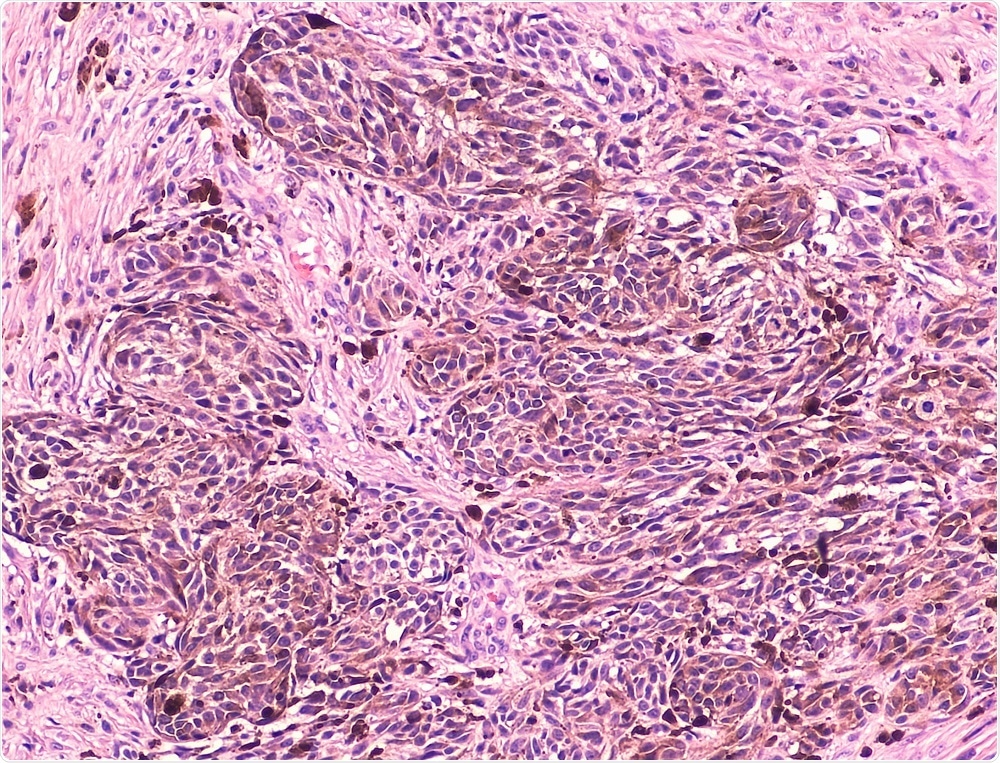

The researchers found that low levels of VDR gene expression occurred in tumors with higher growth rates, whether primary or metastatic melanomas. In addition, low levels of vitamin D also seemed to be linked to the inhibition of genes that regulate cancer-fighting immune responses in the body. In turn, such tumors showed lower numbers of immune cells, particularly of tumor-infiltrating lymphocytes (TILs) on microscopic examination.